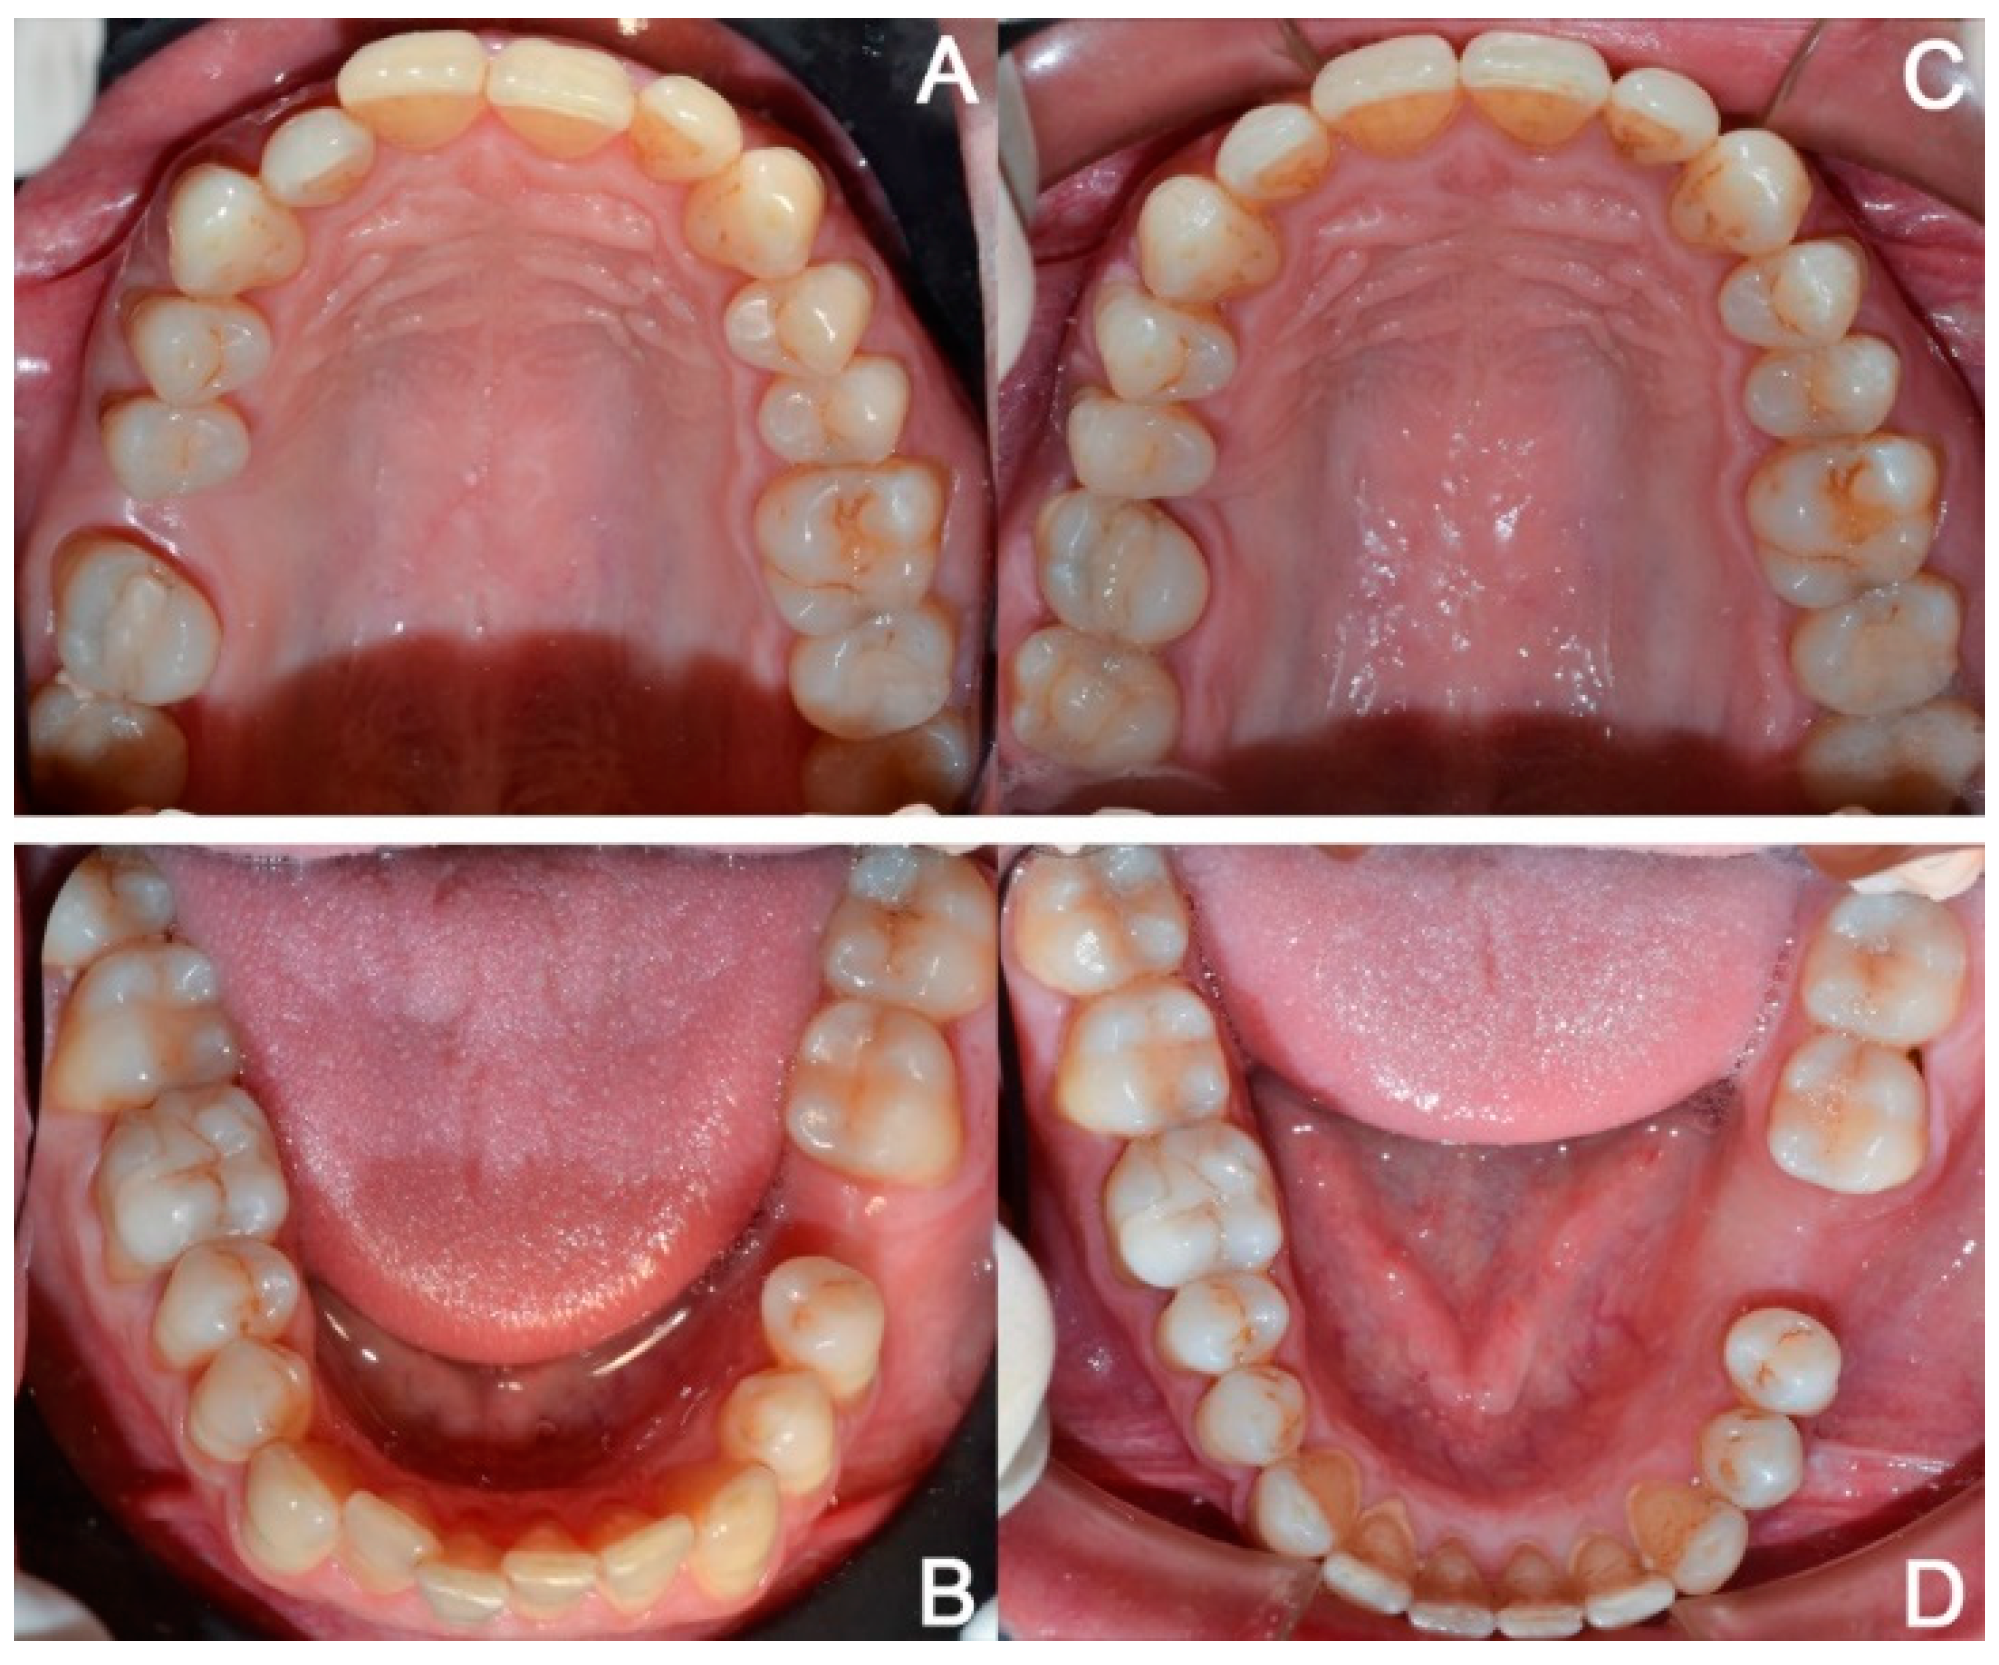

2.3.1. Example—Anterior Open-bite

2.3.2. Example 2—Extraction Space Closure